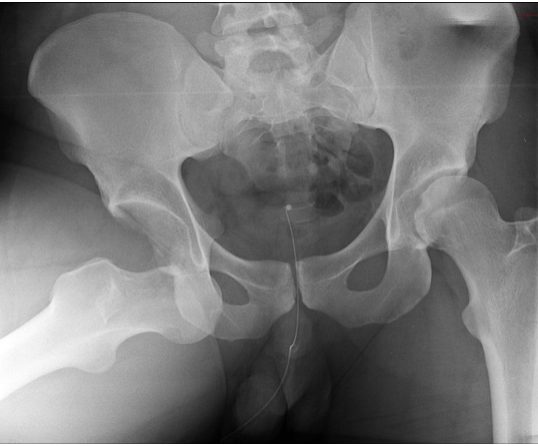

Рентген малого таза широко применяется для исследования органов мочеполовой системы и системы половых органов у женщин, при этом чаще всего прибегают к использованию гистеросальпингографии и пельвиграфии. Что это за исследования:

- Гистеросальпингография – это исследование матки и маточных труб. В них вводится рентгенконтрастное вещество, делается один или несколько снимков. По полученным снимкам врач может оценить состояние внутренних половых органов женщины и диагностировать бесплодие (при непроходимости маточных труб) или другие патологии.